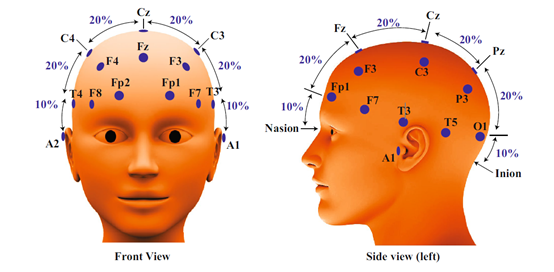

在采集过程中,被试一般直坐在椅子上,记录味觉任务过程中的EEG信号。电极放置采用国际标准10-20电极系统,由味觉刺激诱发的脑电电位称为事件相关电位(ERP),头皮区域需要用尽可能多的电极进行记录,以获取不同脑区的EEG活动,缩短记录系统的电路,可以有效避免电器噪声。原始EEG包含了兴奋性突触后电流(EPSP)、抑制性突触后电流(IPSP)和伪影噪声(需要去除)。电极通道越多则分析产生的误差越少,一般至少需要16个通道才能获得有分类信息的EEG。目前大多数用64电极系统甚至更多电极通道来提高信号记录效率并降低系统噪声。一般需要足够数量的参与者和重复测试试验次数,以保证结果的可重复性和信噪比(SNR)。EEG中提取味觉信息的提取可以采用时域、频域或时频域的方法。

10/20电极系统的电极位置

在10/20电极系统中,电极按照标签F、C、T、P和O分别放置在额叶,中央,颞叶,后叶和枕叶区域,参考电极一般放置在耳后乳突骨或耳垂。利用计算机辅助软件应用程序,以提高记录ERP的时间精确性,同时应减少所有可能的噪声源以获得高质量数据。